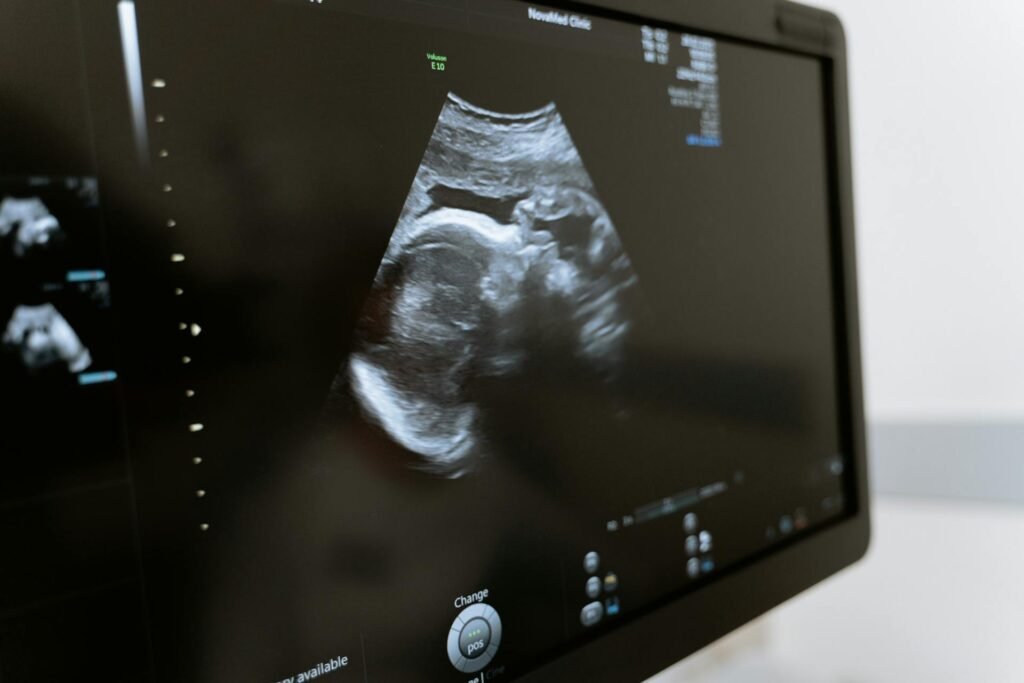

USG połówkowe, nazywane także USG prenatalnym, to jedno z najważniejszych badań w trakcje ciąży. Jest przeprowadzane zazwyczaj między 18. a 22. tygodniem ciąży, a jego głównym celem jest dokładna ocena anatomii dziecka. Podczas badania ginekolog sprawdza między innymi rozwój narządów wewnętrznych maluszka, takich jak mózg, nerki czy wątroba. Na podstawie badania obrazowego jest także w stanie ocenić strukturę twarzy, kręgosłupa i kończyn.

USG w 20 tygodniu ciąży pozwala nie tylko monitorować ogólny stan dziecka, ale także wykryć potencjalne wady rozwojowe. Przyszła mama może otrzymać szczegółowe informacje o rozwoju cech fizycznych swojej pociechy, a także uzyskać fachową pomoc w przypadku, gdy badanie wykaże nieprawidłowości. Jak wygląda samo badanie? USG połówkowe jest bezbolesne i bezinwazyjne. Lekarz wykonuje je za pomocą sondy przykładanej do brzucha, co pozwala na uzyskanie dokładnych obrazów płodu. Więcej informacji na temat badania znajdziesz pod linkiem: https://hipp.pl/ciaza/poradnik/badania-w-ciazy/usg-polowkowe.